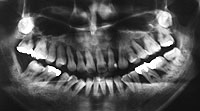

(1)まず、お口全体がわかるレントゲンを取ります。

![]() |

| 正常な骨の状態(根のまわりを白いモヤモヤ(骨)がおおっています) | 骨が溶けてなくなっています(20代女性)(根のまわりが黒く、骨がありません) |

なぜなら、レントゲンを撮れば骨が溶けているか、溶けていないかがわかります。

どこの骨が溶けているのか、溶けていないのか場所がわかります。

それがわかるのでどこの歯が重症か、悪化しているのかがわかるわけです。

どこの部分の歯周病菌の種類を調べてやればいいのか、わかるのです。

そこの歯周病菌の種類を調べてやれば大体、口の中は感染症だから原因の歯周病が何かわかるわけです。